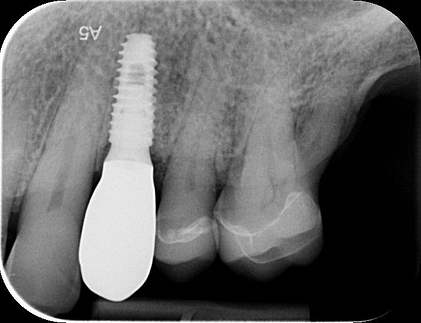

To better understand the patient's overall dental health, a full mouth CBCT scan was taken, confirming the presence of a bony defect in the area where tooth 24 had been surgically extracted.

Intraoral scans were completed using the Trios 4 intraoral scanner and a H8 x D 15cm craniofacial field CBCT was taken.

Pre-surgical planning began with acquiring high-quality diagnostic data, including TRIOS intraoral scans and CBCT imaging. The data was imported into 3Shape Implant Studio, where I designed a virtual crown for tooth 24 and planned the precise positioning of the implant, considering critical factors such as sinus proximity, adjacent roots, bone density, and the location of the bony defect.

A radiographic assessment confirmed the proper integration and positioning of the implant.